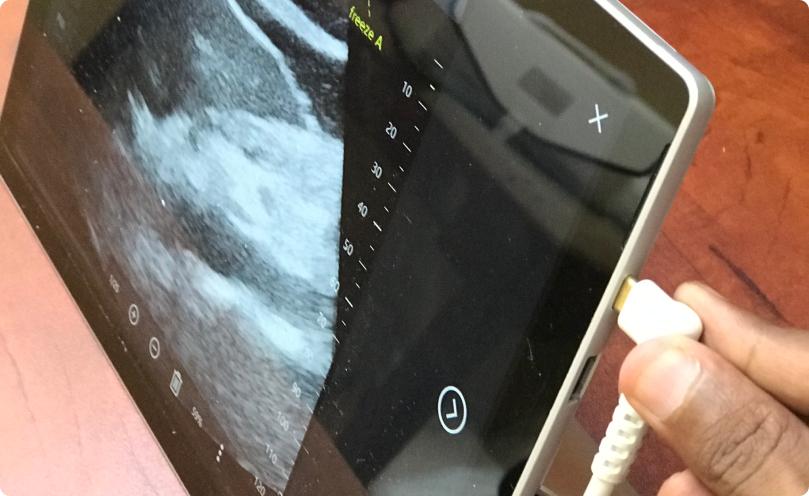

LumaLife’s AI-powered, patent-pending diagnostic platform redefines care for liver and kidney patients—bringing results comparable to CT Scanners using harmless Ultrasound technology. By reducing costs by up to 90% and removing the burden of travel, it ensures access for even the most underserved communities.

With guided scans performed remotely, specialists can now be provided with insights, enabling early detection and faster treatment. From rural villages to advanced hospitals, this ultra-portable solution bridges critical gaps in healthcare—offering a new standard of affordability, mobility, and clinical precision.

Developed an Ultrasound Visualization & Diagnostic System that integrates AI for precision, speed, and ease of use.